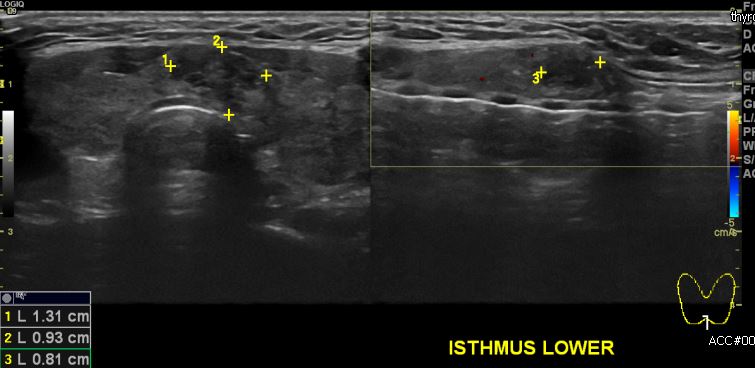

상기 환자 목의 답답함으로 내원하신 30대 여성분으로 본원 갑상선 초음파 후 갑상선

협부에 의심스러운 멍울 조직검사 시행하여 갑상선 유두암 진단 되었습니다.